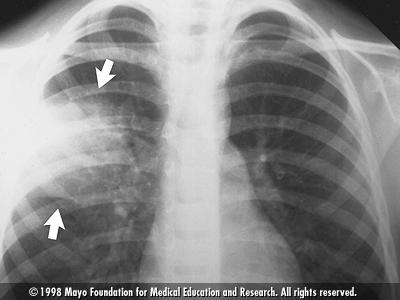

يحتاج بعض المرضى لإجراء فحوص مخبرية مثل صورة أشعة سينية للرئتين وفحص شامل للدم، بالاضافة إلى تحليل للبلغم

– أن يصيب الالتهاب فصآ واحدآ أو جزءآ من الفص وتسمى الحالة (Lobar Pneumonia)

– أن يصيب أجزاءآ من الرئتين وتسمى الحالة (Bronch Pneumonia)